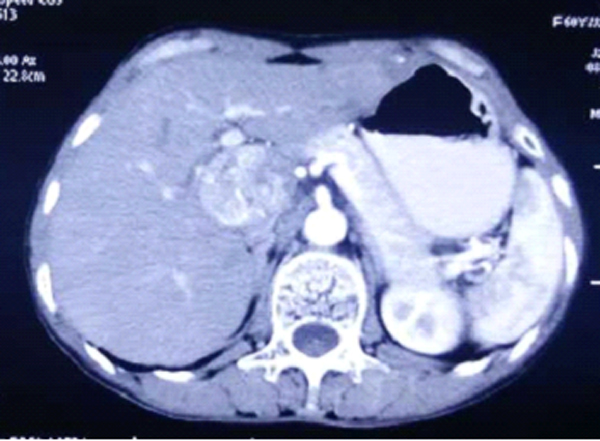

患者女性,58岁,因查体发现肝占位10天入院,腹部强化CT显示肝门区占位,考虑肝癌,患者有长期乙肝病史,AFP指标升高,诊断为尾状叶的原发性肝癌。,齐鲁医院普外科F5C病房经过科室讨论,决定行腹腔镜肝尾状叶肿瘤切除术,手术由胡三元教授、靳斌副教授、杜刚主治医师、付志浩医师、周兵海医师实施,术中情况:腹腔内无腹水,腹壁、盆腔未见转移结节,肝脏呈结节性肝硬化表现,肿瘤位于肝脏尾状叶,约5×5cm,与周围有粘连,术中解剖第三肝门,分别从左、右两侧解剖出多支下腔静脉通向尾状叶的肝短血管,以hem-o-lock夹夹闭后离断,解剖第一肝门,解剖出肝动脉、门静脉通向肝脏尾状叶的血管,分别以hem-o-lock夹夹闭,可见尾状叶颜色变暗,于第一肝门置入特制的“蛇形”牵引器,将其牵向右侧,然后离断尾状叶肿瘤的左侧,大的血管及胆管以hem-o-lock夹夹闭后离断,以同样方法处理尾状叶肿瘤的右侧,将肝脏尾状叶肿瘤切除。手术时间2小时余,术中出血约100ml,术后第1天患者进食并下床活动。术后病理示:(肝)中分化肝细胞肝癌,手术切缘未查见癌。